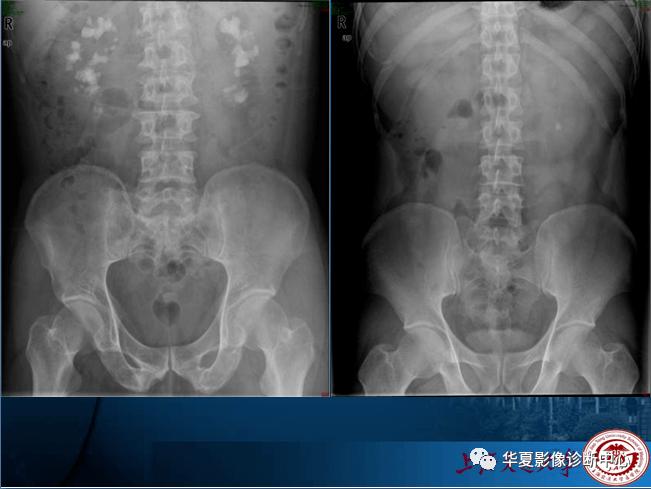

正常腹部平片,正常腹部x线平片图

正常腹部平片 腹壁及腹内器官均 为软组织结构,缺 乏自然对比 府谷县

正常腹部x线平片图

正常腹部平片图片

正常腹部平片影像表现